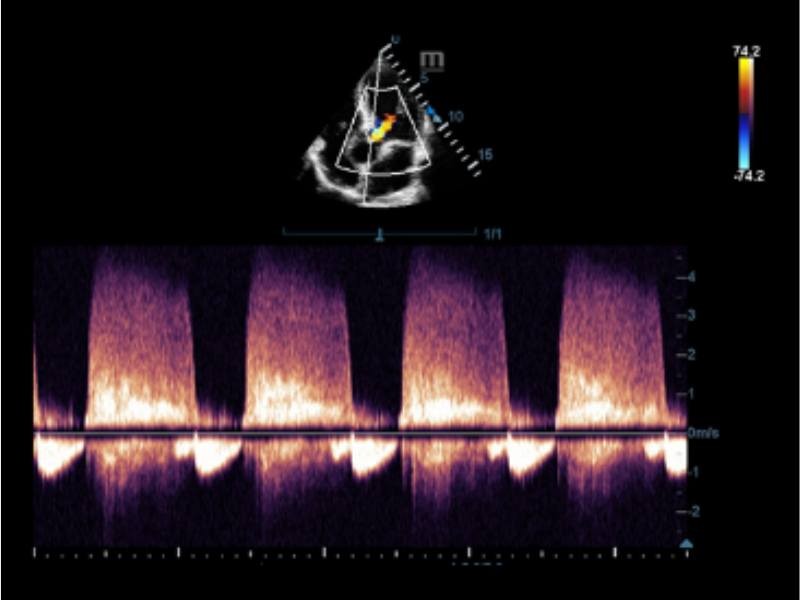

Trilha Inteligente

O Smart Track proporciona uma otimização rápida e inteligente das imagens vasculares com apenas um toque. Ele pode otimizar o espectro de cor, energia e PW por meio de rastreamento automático e reduz as etapas demoradas. Portanto, o fluxo de trabalho do exame vascular é simplificado por meio de uma visão ideal.